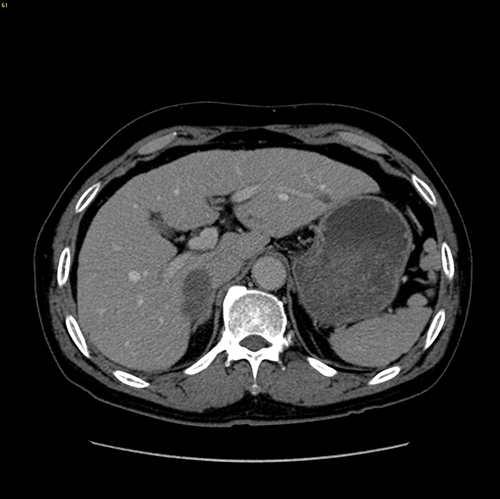

S678肝癌 ---腹腔镜右半肝切除